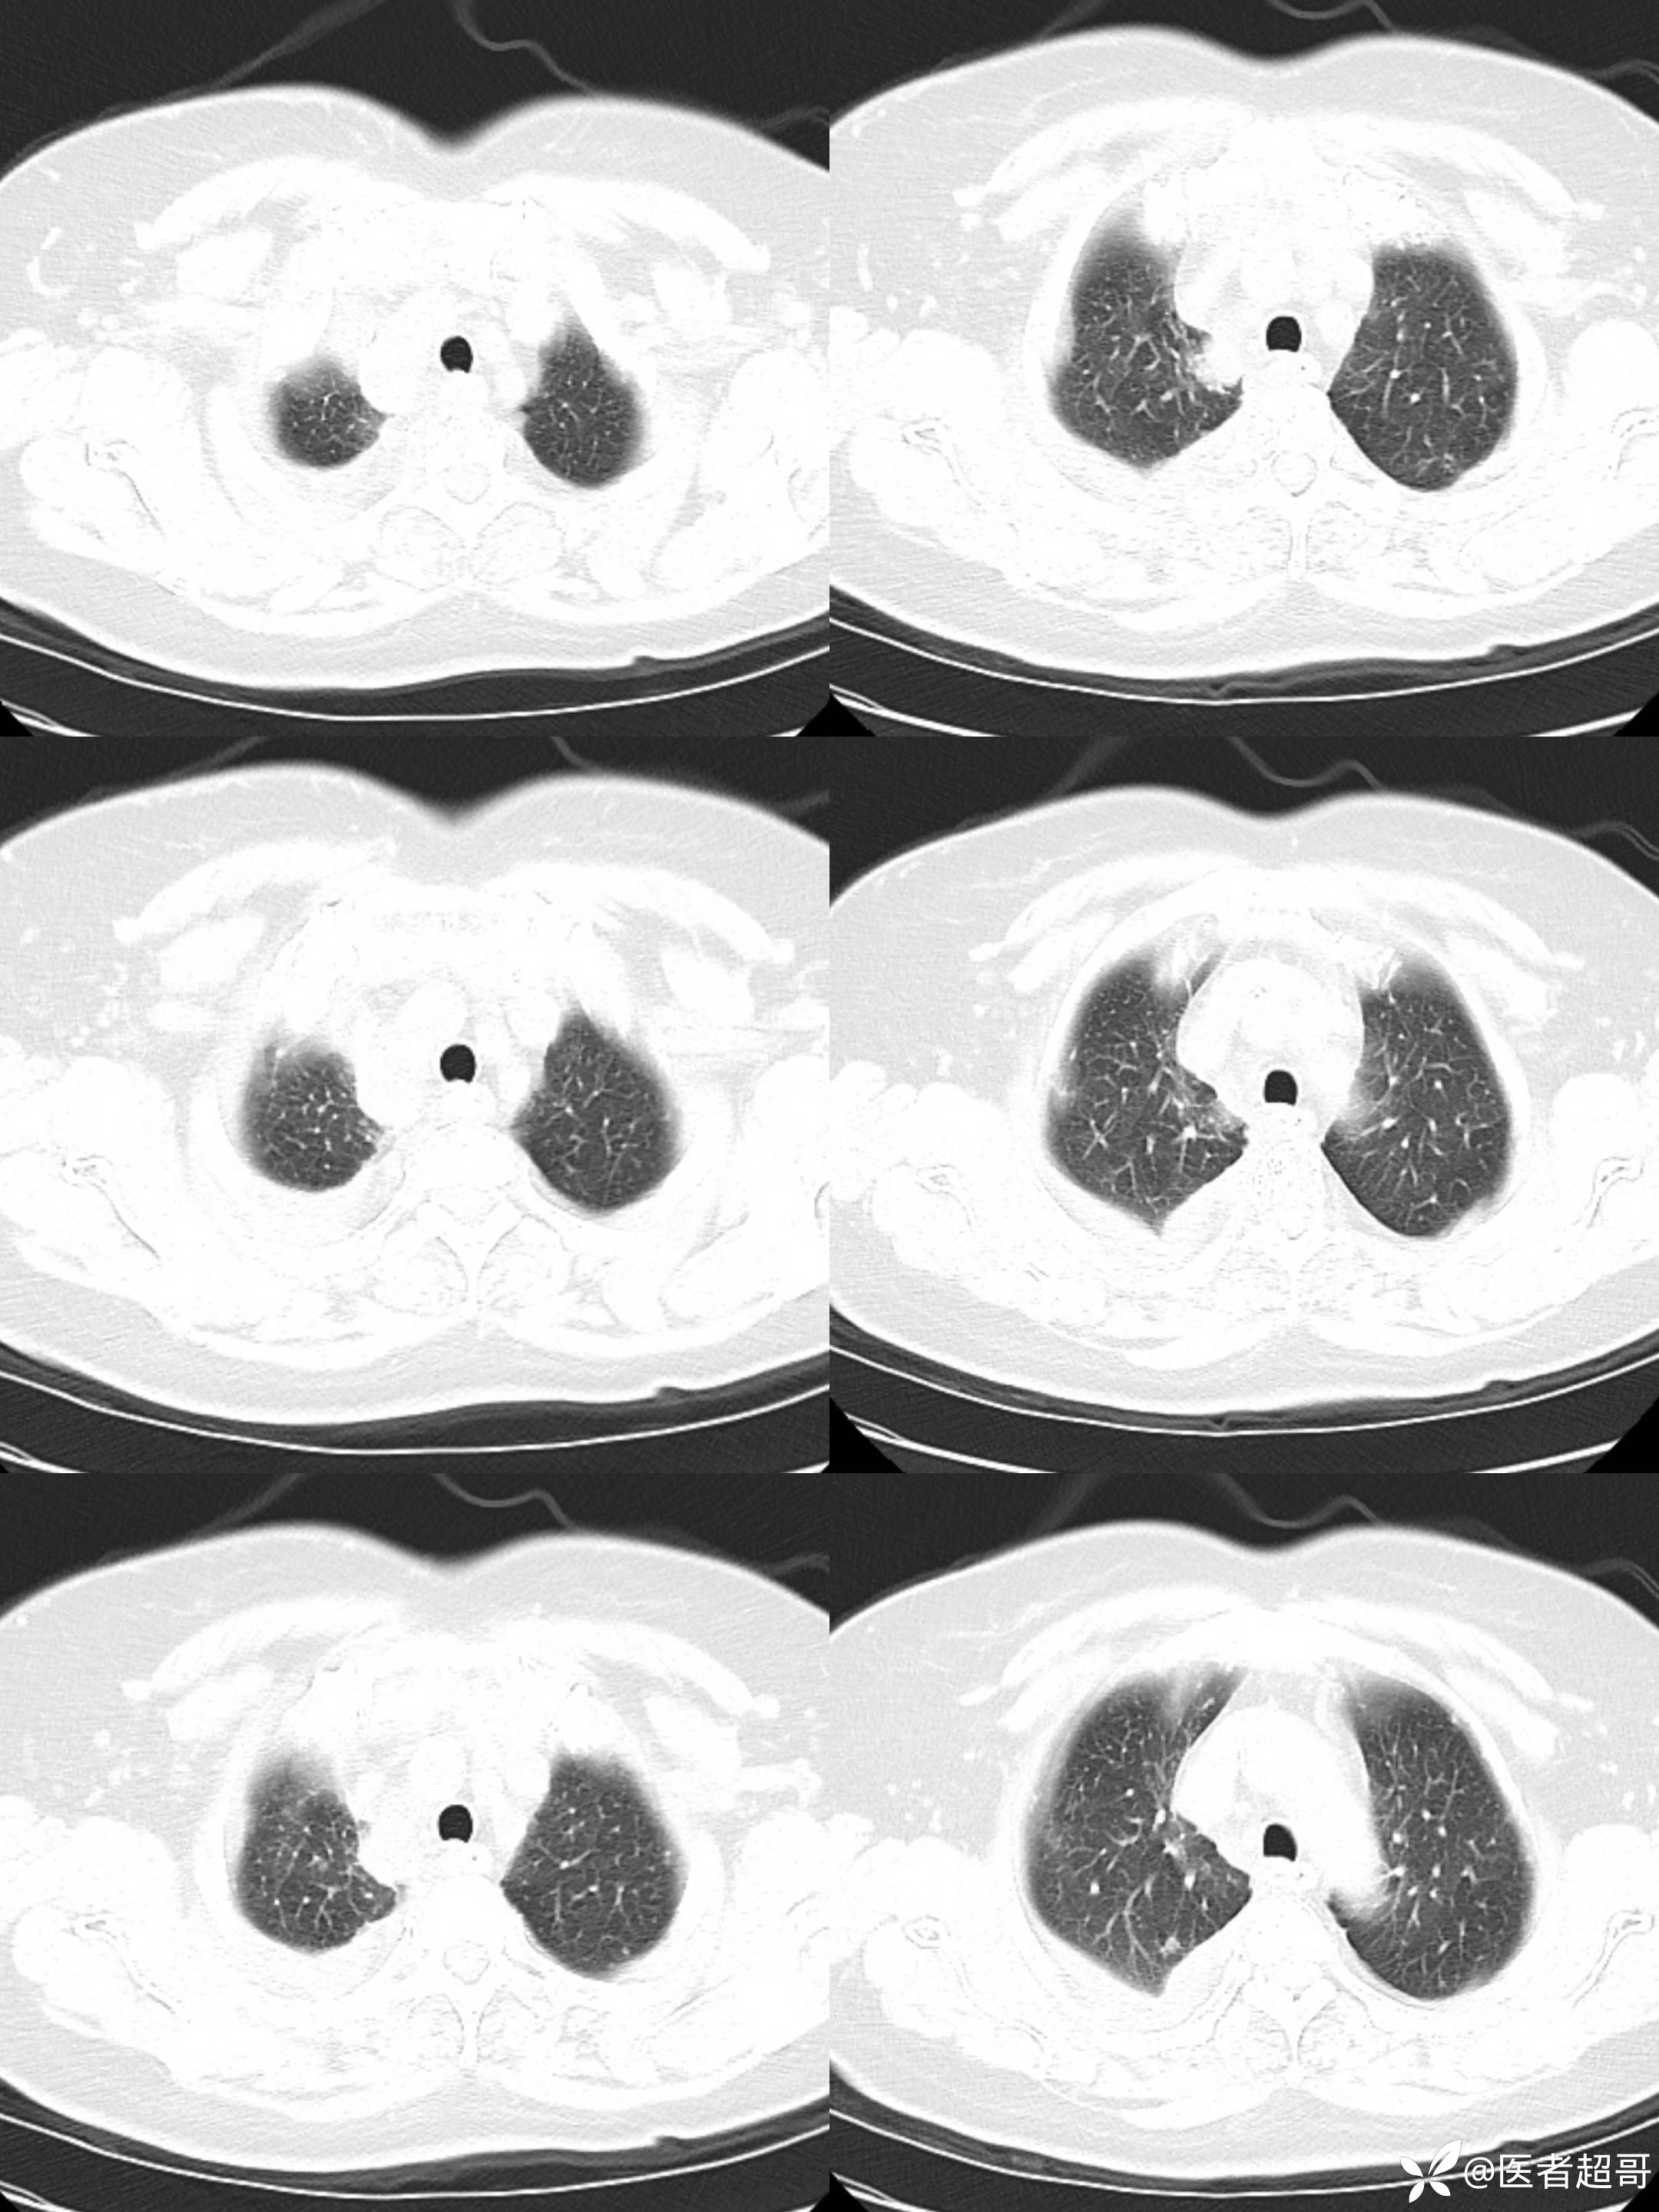

女65岁,患者于一月前无明显诱因突发右胸背部疼痛不适,呈阵发性疼痛

结核特异性细胞(TB-I) 阴性;超敏反应C蛋白(hsCR) 18mg/L ↑,其余血常规正常;

纵隔良性畸胎瘤 (1)